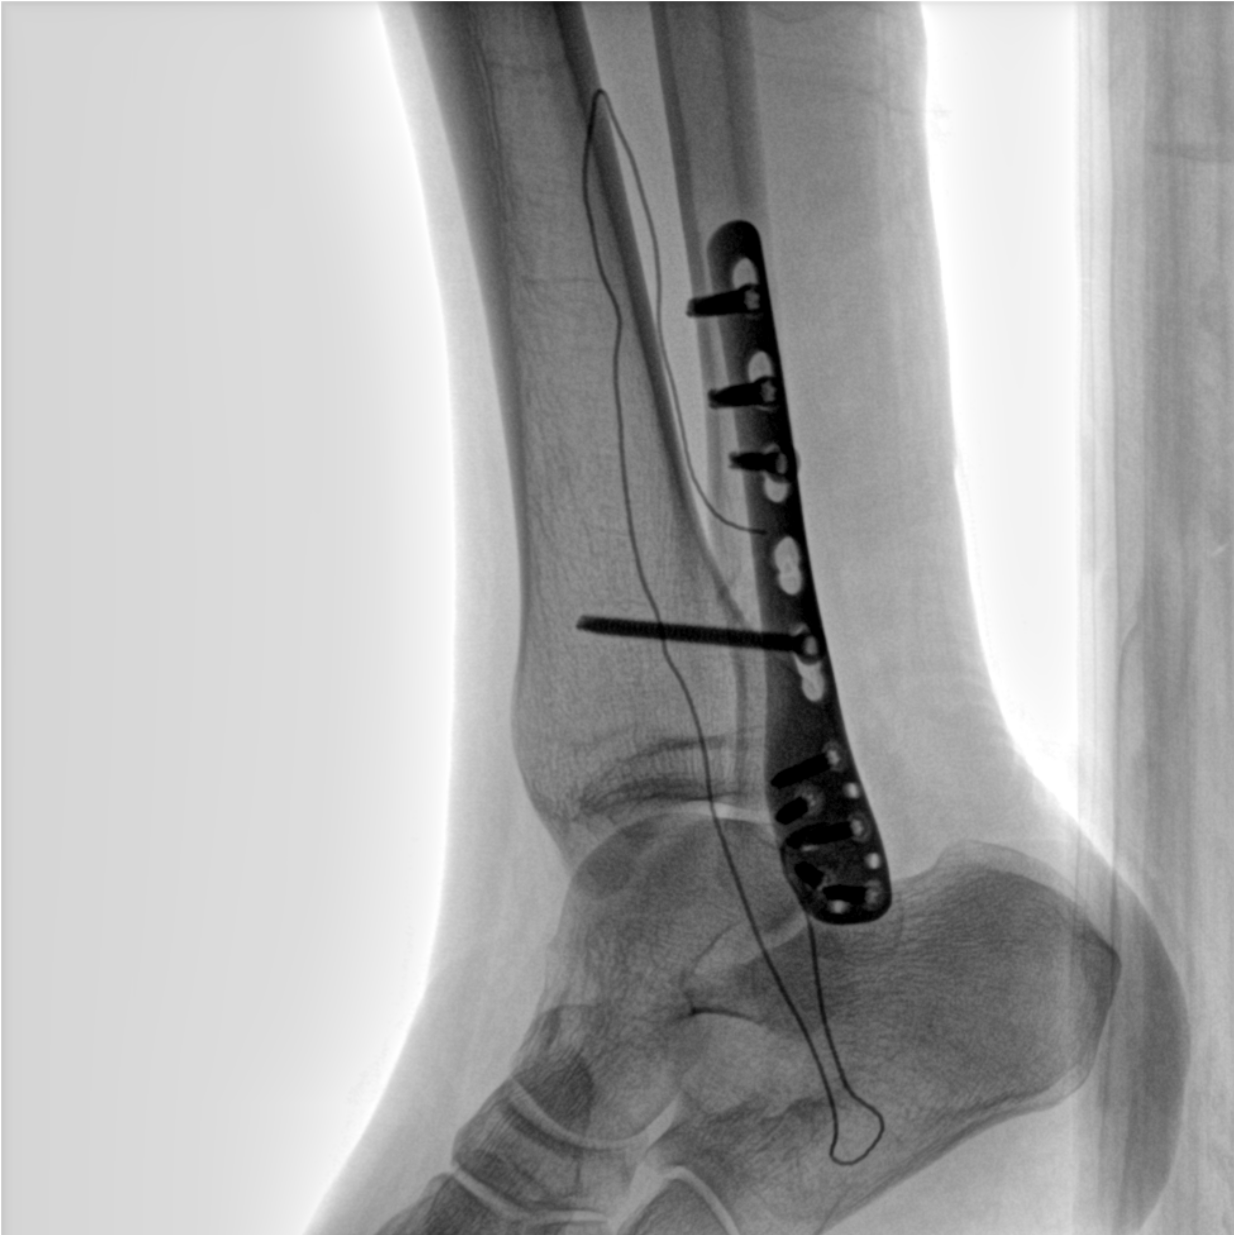

術(shù)中三維成像和橫斷面圖像提供多角度的手術(shù)診斷信息,輔助醫(yī)生進(jìn)行術(shù)中評(píng)估判斷,諸如骨折復(fù)位情況和內(nèi)植入螺釘?shù)某叽绾臀恢?,輔助手術(shù)更好地完成。